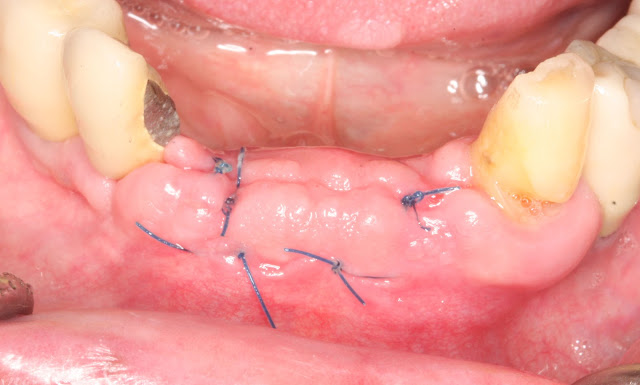

Re-surgery following implant fracture

This year, a 74-year-old male patient visited us with a mini dental implant that had been placed in the lower jaw.

After 4 years of prosthetic use, one of the implants came loose and torn as seen in the picture.

The patient had a bar overdenture in place over the edentulous ridge.